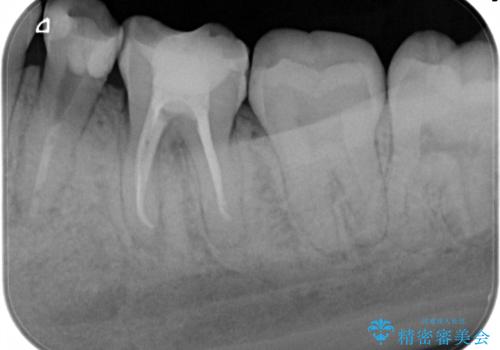

精密根管治療。大臼歯イニシャルケース

- 奥歯がズキズキ痛いことを主訴に来院されました。

検査の結果、診断を症候性不可逆性歯髄炎、症候性根尖性歯周炎とし抜髄を行っております。

根管充填はCWCTにて行なっております。

根管形成はマルテンサイト相を有するNi-Tiロータリーファイル(NEX MS)使用。